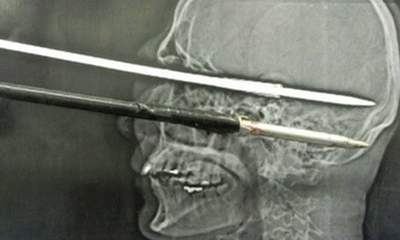

Φτηνά τη γλίτωσε ένας Βραζιλιάνος που μεταφέρθηκε στο νοσοκομείο με ένα καμάκι να έχει διαπεράσει το κρανίο του! Ο Μπρούνο Κουτίνιο καθάριζε το ψαροντούφεκό του στο σπίτι του, όταν άθελά του πάτησε τη σκανδάλη.

Το μήκους 15 εκ. καμάκι διαπέρασε το αριστερό του μάτι και το κρανίο του. Οι γιατροί χρειάστηκαν τέσσερις ώρες για να αφαιρέσουν το μεταλλικό αντικείμενο, αφού η κατάστασή του απαιτούσε διπλή επέμβαση, με τον ασθενή να έχει το αντικείμενο για δέκα ώρες στο κεφάλι του.

Σύμφωνα με τον επικεφαλής της νευροχειρουργικής κλινικής του νοσοκομείου, το καμάκι απείχε μόλις χιλιοστά από τη βασική αρτηρία στο κεφάλι του άνδρα. Ο Βραζιλιάνος στάθηκε τυχερός καθώς δεν έπαθε εγκεφαλική βλάβη, αν και έχασε την όραση από το αριστερό του μάτι. Παρόλα αυτά, αναμένεται να πάρει εξιτήριο τις επόμενες ημέρες.